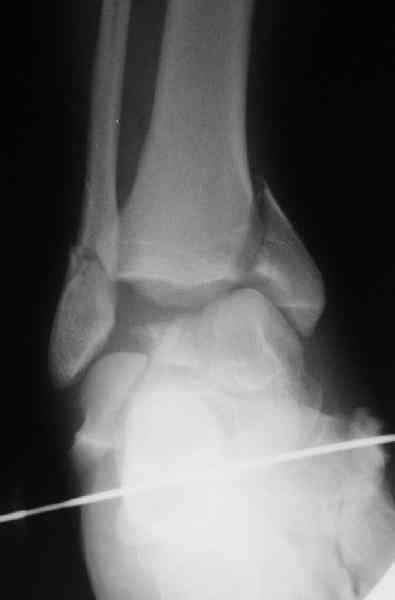

И второй случай из недавней ташкентской практики, (извините за качество ренгенограммы и только в одной проекции) случай падения с высоты (кстати моего друга - известного киноактера) - открытый

смещенный перелом тарана, с переломом переднего края дистального эпиметафиза большеберцовой кости.

При поступлении в приемной сделана первичная обработка с ушиванием открытой латеральной раны и вытяжением за пятку.

Из-за отсутствия времени пришлось оперировать на второе утро, из материала, что имеем на месте, фиксирован двумя шурупами, а третий-это контур сломанного жойстика в 4 мм. На дистальный медиальный конец тибиа antiglide 3.5 мм пластина. Через пару дней выписан и несмотря на предупреждение, самостоятельно начал нагрузку в 4 недели, время не ждет, снимается в боевике в Росийской Федерации.